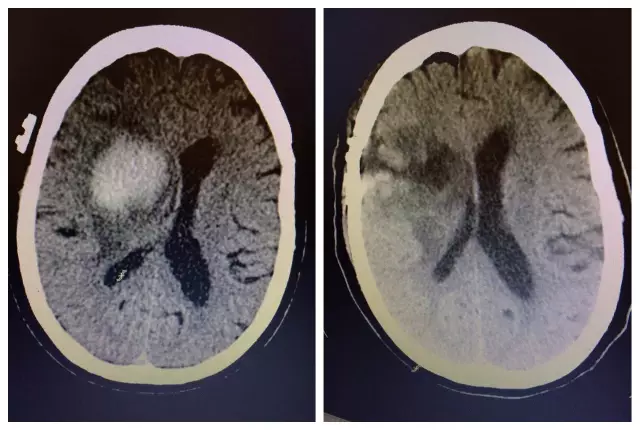

惠州市民周阿姨現(xiàn)年60歲,因意識(shí)障礙4小時(shí)入住我院神經(jīng)外科,既往有高血壓及糖尿病史,CT顯示右側(cè)放射冠-基底節(jié)區(qū)腦出血并破入腦室系統(tǒng),腦出血量達(dá)30ml。起病以來(lái),患者精神差,頭痛明顯,左側(cè)肢體偏癱,生活完全不能自理。

對(duì)于手術(shù)治療,家屬一直心存疑慮,經(jīng)過(guò)醫(yī)生不厭其煩地講解病情后才同意手術(shù)??紤]到患者年齡大,血腫位置深,主刀醫(yī)生文世宏主任率先采用微球囊及內(nèi)鏡輔助為其進(jìn)行了血腫清除術(shù),手術(shù)獲得圓滿成功,血腫完全消失,術(shù)后患者精神明顯好轉(zhuǎn),頭痛消失,肢體活動(dòng)也有了明顯的改善,進(jìn)一步康復(fù)有望生活完全自理。家屬對(duì)手術(shù)效果十分滿意,夸贊這個(gè)手術(shù)真是太神奇了?。?!

術(shù)前CT和術(shù)后CT對(duì)比